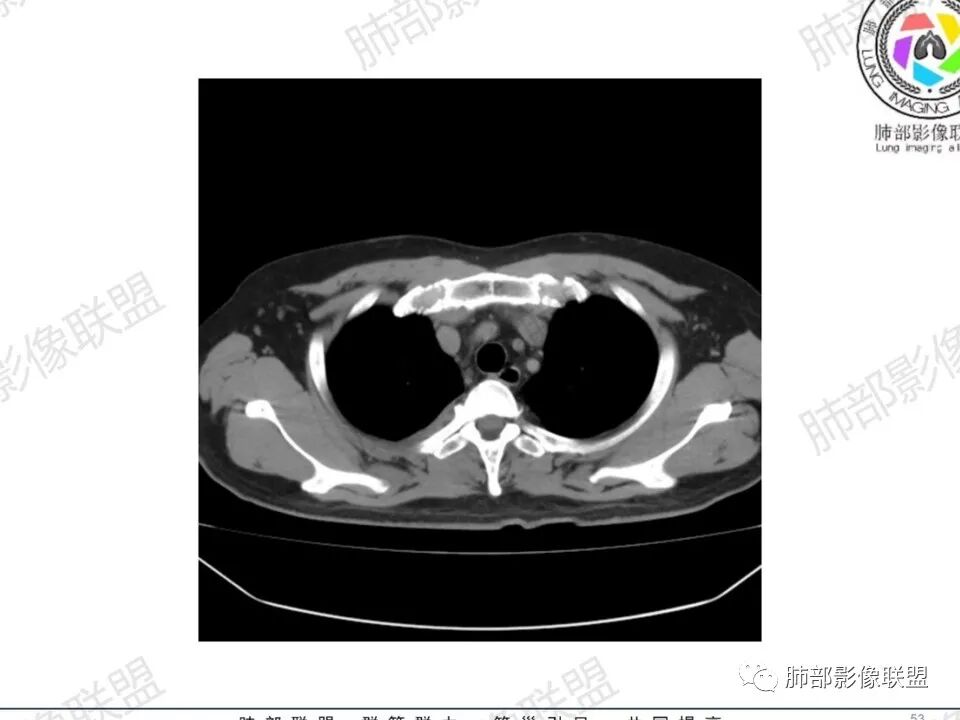

双肺多发结节,胸膜下为主,部分可见空洞。左肺上叶尖后段结节较大,分叶毛刺,周围可见长条索及小斑片影,内空洞比较光滑,内侧壁可见支气管通过。右肺下叶后基底段不张实变,后侧积液,右侧水平裂积液,右侧膈胸膜纵膈胸膜增厚积液,右侧侧胸膜肥厚,考虑1:一元金葡。2二元:金葡,左肺上叶结核。

中年男性,左手中指及胸壁疼痛伴发热来诊,影像见双肺多发结节,胸膜下分布为主,部分结节可见空洞,边缘模糊。左肺上叶尖后段结节较大。右肺下叶后基底段不张实变,右侧叶间裂及右侧胸腔积液,右侧侧胸膜肥厚。考虑金葡菌感染,血播SPE。